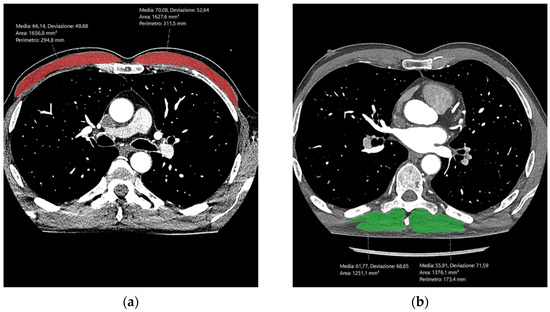

1. Introduction

2. Materials and Methods

2.3. CCTA Image Evaluation